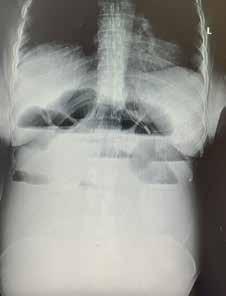

A case report of acute intestinal obstruction in third trimester of pregnancy – a diagnostic challenge - 29